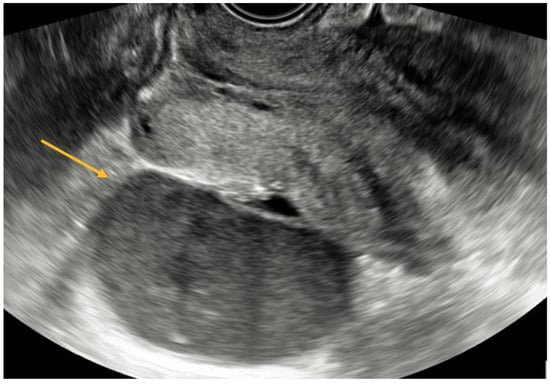

USL endometriosis involvement is usually diagnosed by TVS when assessing the posterior pelvic compartment. USL lesions appear as depicted in Figure 5, as a linear hypoechoic thickening exhibiting either regular or irregular edges [9]. Particularly, we have noticed the nodule appears to have a high-echoic appearance compared to what is commonly described in the relevant literature. However, it is important to highlight that the contour and demarcation of the surrounding structures are clearly discernible.

USL lesions are usually linked to concurrent DIE lesions, the arrow in Figure 5 indicating the presence of a USL nodule connected to a uterine torus DIE lesion. The section indicated by asterisks represents the measurement of the length of the lesions.

Figure 5. TVS aspect of uterine torus and USL endometriosis lesions.